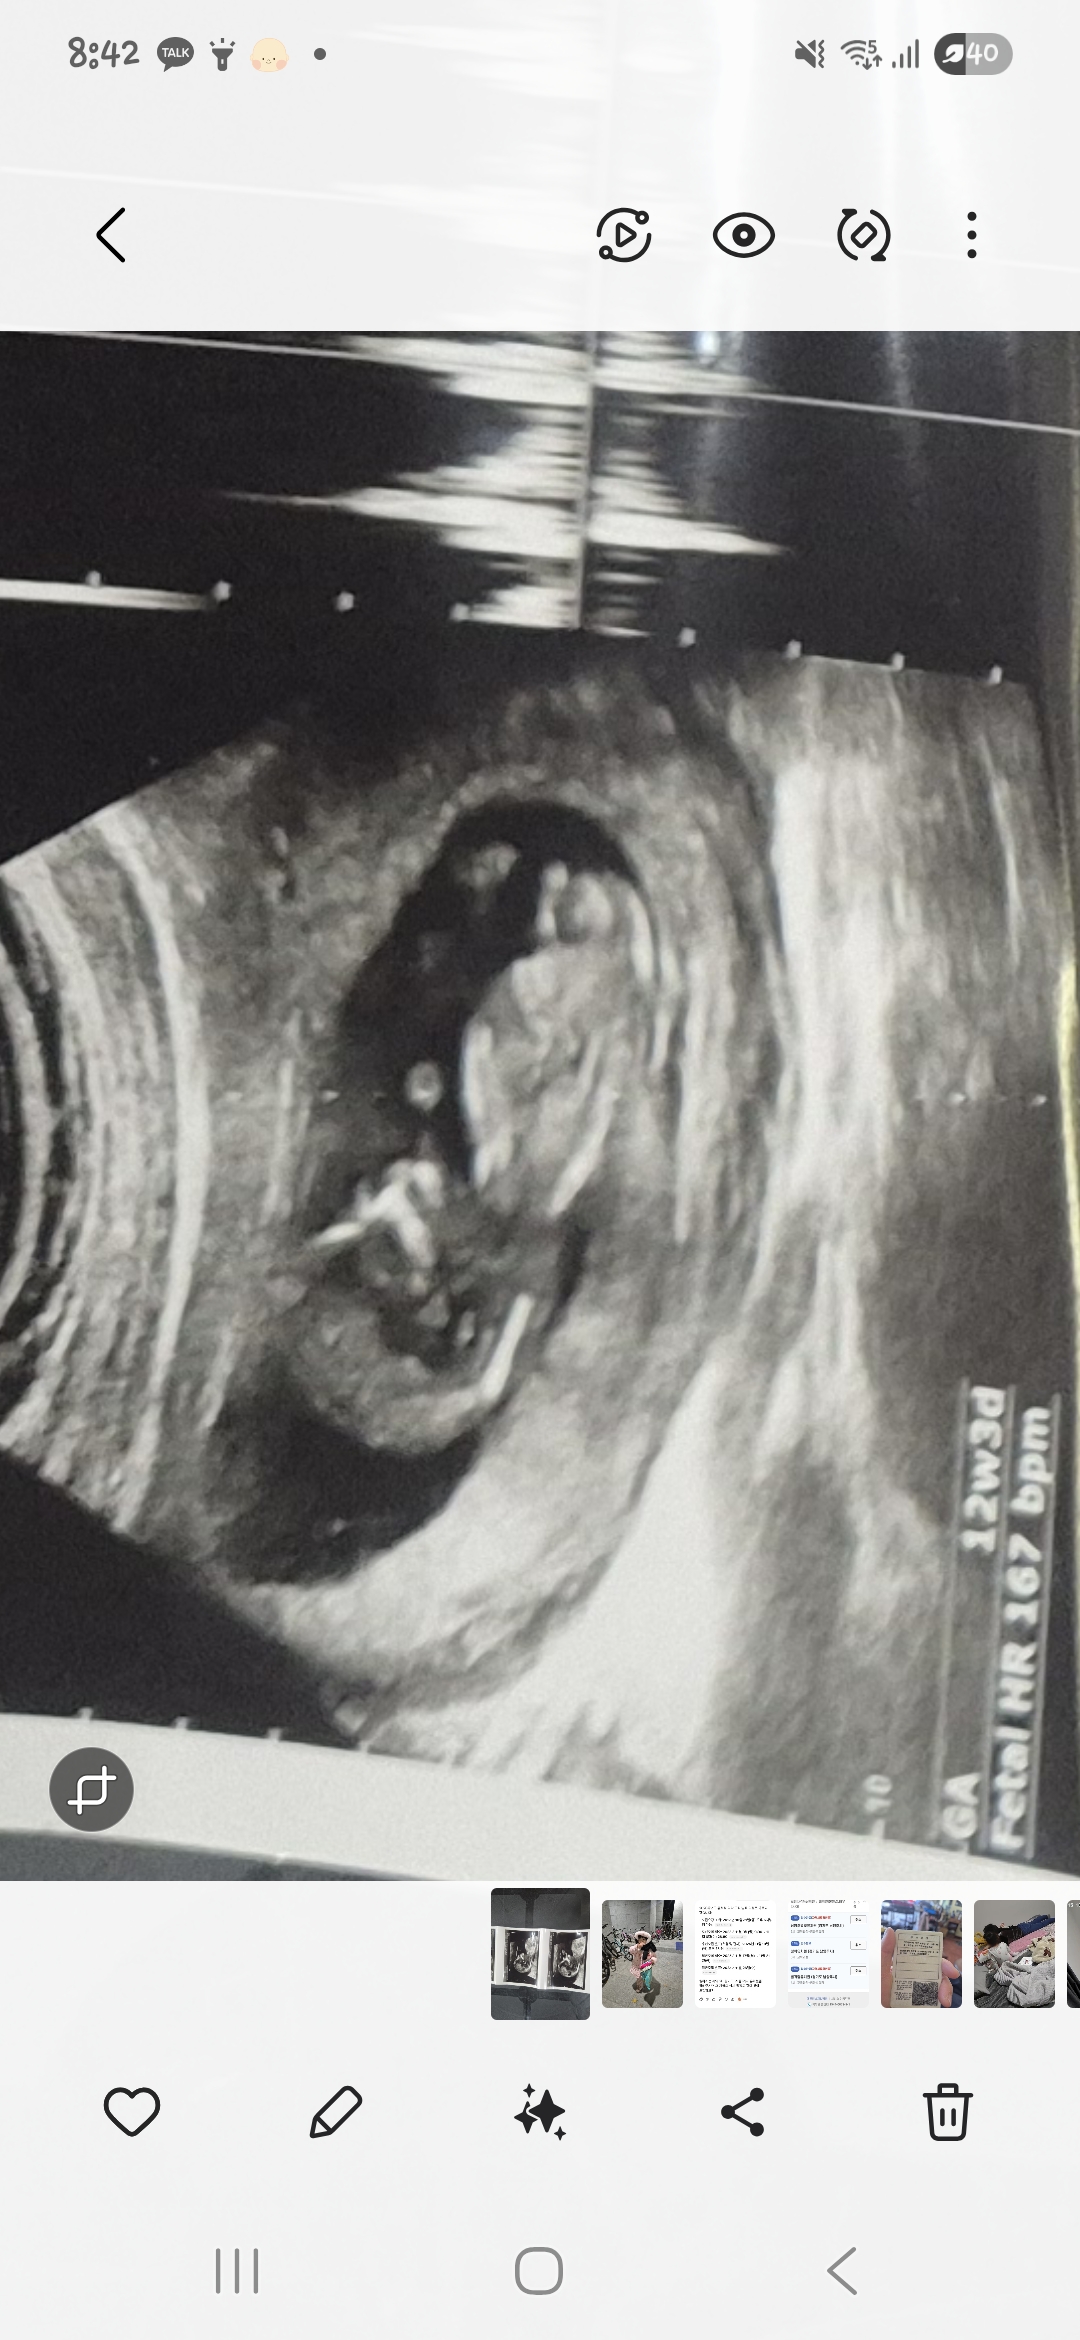

쳇지티p는 딸같다는데요 참견부탁드려요

12주5일됫는데 여려분의견을듣고싶어요..♡ 참견부탁드려요., 첫째가딸이라 아들을 원하는데ㅎㅎㅎ 주변서태몽을안꿔준 케이스라.. ㅎㅎㅎ